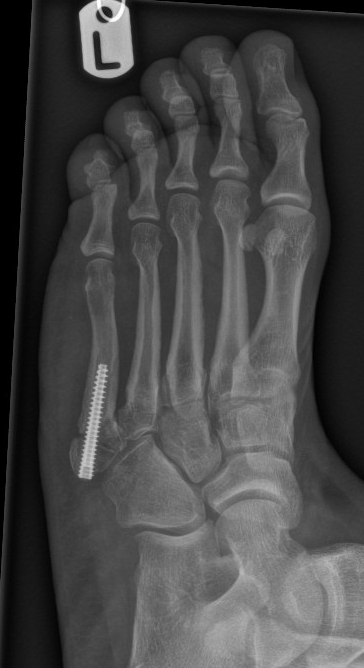

Case 2 - delayed presentation of inversion injury

Figure 4: Discplaced, intra-articular, communted fracture with signs of early sclerosis

Figure 5: 3 months following compression screw fixation with signs of early failure / non-union

Figure 6: 3 months following revision fixation and cancellous autograft (from heel)